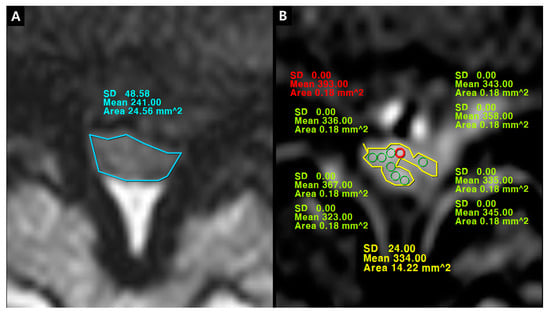

Figure 7. Signal intensity measurement of psoas muscle on fat-suppressed enhanced T1-weighted axial image. (A,B) Psoas1, manually-defined region of interests (ROIs); (C,D) Psoas2, circular ROIs.

The quantification of IRCE was evaluated by the ratio (%) of signal intensities between the cauda equina and psoas muscle on the same axial enhanced image. The signal intensity of rootlets was measured within the manually defined region of interests (ROIs) along the boundary of the white signal by a digitizer, Maroview software (Infinitt Healthcare Co., Seoul, Korea). To define an exact margin, intrathecal rootlets were marked on the same T2-weighted axial image. The adjustment of the gray scale (window level) was necessary for the discrimination between the rootlets and cerebrospinal fluid. Manual ROI analysis was performed by superimposing previously acquired ROI on the enhanced fat-suppressed T1-weighted image (Figure 5). Two methods were composed of whole rootlets IRCE (WR-IRCE) and maximal spot rootlet IRCE (MS-IRCE) at the most stenotic level (Figure 6). WR-IRCE was obtained by recording the mean signal intensities of all outlined intrathecal rootlets. MS-IRCE was defined as the maximum value in circular ROIs (0.18 mm2) among intrathecal rootlets. In some patients, the large radiculomedullary veins showed strikingly higher signal intensities (>315) than those of other rootlets. These high signals were excluded in the subsequent measurements. The measurement of WR-IRCE and MS-IRCE on the L3–4 and L4–5 levels, respectively, were also performed in the asymptomatic control group to find a difference between such levels. The signal intensity measurement of the psoas muscle was performed within manually defined ROIs (Psoas1), which were delineated along the margin of the unilateral psoas muscle on the same enhanced axial images. In addition, circular ROIs (33.42 mm2, Psoas2) were designated within the medial portion of the psoas muscle corresponding to a mid to posterior disc space to avoid field inhomogeneity (Figure 7). Using these signal intensities, four rootlet-to-psoas ratios were defined (MS/P1 = MS-IRCE/Psoas1*100, WR/P1 = WR-IRCE/Psoas1*100, MS/P2 = MS-IRCE/Psoas2*100, WR/P2 = WR-IRCE/Psoas2*100). Those parameters were analyzed to identify the best possible candidate to stratify patients with lumbar central stenosis.